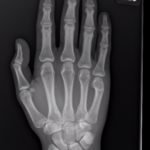

Significant findings:

A two-view radiograph of the right hand was obtained which revealed a dorsal dislocation of the distal fourth and fifth metacarpals (see red and blue outline, respectively) with a concomitant fracture of the distal fifth metacarpal (see yellow line) and avulsion fracture of the lateral aspect of the hamate (see green line). After reduction the fourth and fifth metacarpal dislocations are resolved; however, the distal fifth metacarpal fracture (yellow line) and avulsion fracture of the lateral aspect of the hamate (green line) are still visible.